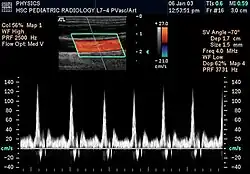

Непрерывная (постоянноволновая) ПСД

Основана на постоянном излучении и постоянном приёме отражённых ультразвуковых волн. При этом величина сдвига частоты отражённого сигнала определяется движением всех структур на пути ультразвукового луча в пределах глубины его проникновения.

- Недостаток: невозможность изолированного анализа потоков в строго определённом месте.

- Достоинства: допускает измерение больших скоростей потоков крови.